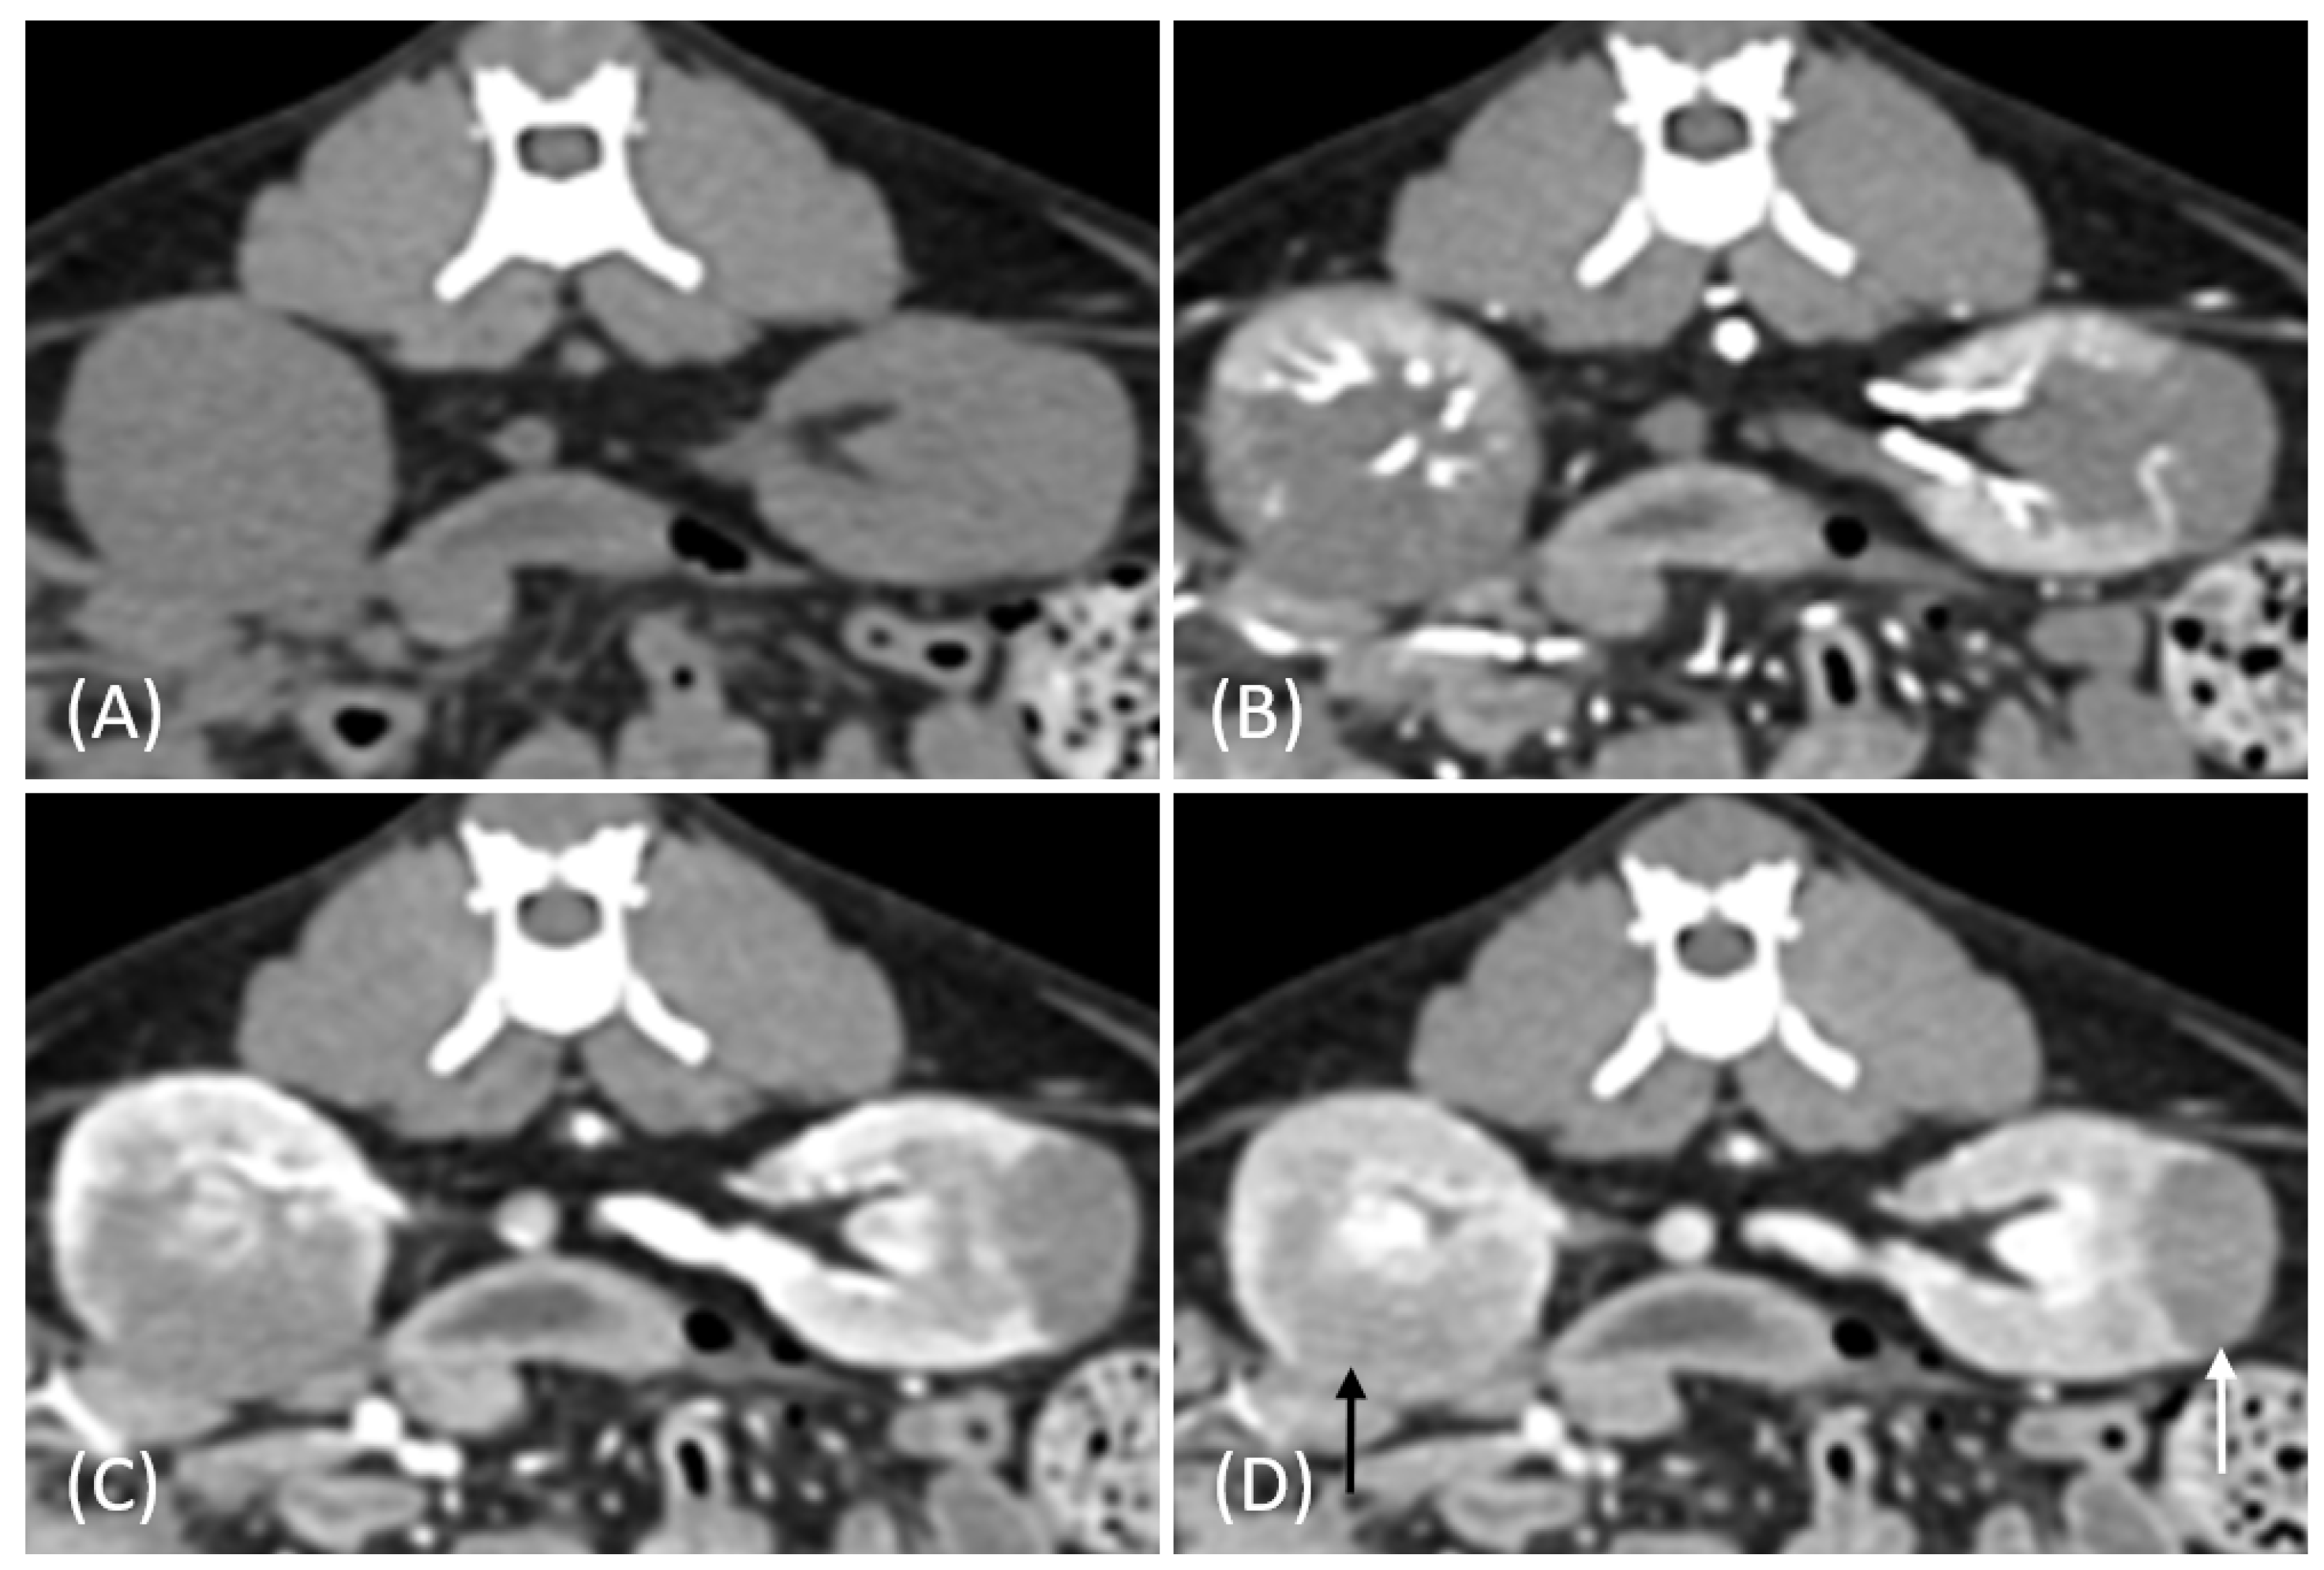

Figure 3.

(A) Pre-contrast, (B) corticomedullary phase, (C) nephrographic phase, and (D) delayed nephrographic/early excretory phase contrast-enhanced computed tomography (CT) images of a cat with bilateral renal and small intestinal lymphoma. The right kidney shows an infiltrative mass (black arrow), while the left kidney has an expansile mass (white arrow). Both tumors are homogeneous and hypodense, demonstrating progressive enhancement.

Tumor growth patterns differed significantly between RCC and lymphoma cases (p = 0.015). RCC predominantly exhibited an expansile growth pattern (11/15, 73.3%) (Figure 1 and Figure 2), while infiltrative patterns were observed in three cases (3/15, 20%) and a combined pattern in one case (1/15, 6.7%). In contrast, lymphomas showed more variable patterns, with infiltrative growth being the most common (5/10, 50%), followed by combined (3/10, 30%) and expansile patterns (2/10, 20%) (Figure 3).

The spatial enhancement pattern differed significantly between the two tumor types (p < 0.001), with RCC typically showing heterogeneous enhancement (13/13, 100%) and lymphomas displaying homogeneous enhancement (9/10, 90%). However, one lymphoma case demonstrated a heterogeneous enhancement pattern (Figure 6A). Tumor vessel enhancement in the corticomedullary phase was observed exclusively in the RCC cases (4/5, 80%) (Figure 1B), while none of the lymphoma cases showed this feature (0/6, 0%) (p = 0.015).

The time-course enhancement pattern analysis revealed different characteristics between the RCC and lymphoma cases. Among the RCC cases with available three-phase enhancement data (n = 5), three cases (3/5, 60%) showed a progressive enhancement pattern (Figure 1), while two cases (2/5, 40%) demonstrated a plateau pattern (Figure 2). By contrast, all the lymphoma cases with available data (n = 6) exhibited progressive enhancement patterns. However, the difference in the time-course enhancement patterns between the two tumor types was not statistically significant (p = 0.182).